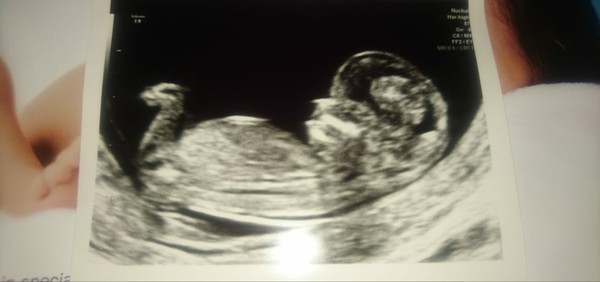

12 weeks 6 days , have had lots of mixed guesses can you give your input please?

Dipsydoodlenoodle · 14/10/2021 10:10

From the skull I'd guess boy and nub girl.

Guessing girl